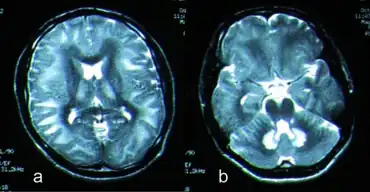

Toxic leukoencephalopathy is a rare condition that is characterized by progressive damage (-pathy) to white matter (-leuko-) in the brain (-encephalo-), particularly myelin, due to causes such as exposure to substance use, environmental toxins, or chemotherapeutic drugs. The prevalence of this disease is infrequent and often goes unreported, especially in cases resulting from substance use. Magnetic resonance imaging (MRI) is a popular method to study and diagnose the disease. However, even with technological advances, the exact mechanism and underlying pathophysiology of toxic leukoencephalopathy remains unknown and is thought to vary between sources of toxicity. The clinical severity of toxic leukoencephalopathy also varies among patients, exposure time, concentration, and purity of the toxic agent. Some reversibility of the condition has been seen in many cases when the toxic agent is removed.

Due to advances in MRI, this neurological disorder has been characterized more successfully in more recent years. MRI can aid in the detection of injured brain tissue; however, the severity and extent of the damage demonstrated by imaging does not always reflect patient clinical status.[8] Toxic leukoencephalopathy encompasses the degeneration of white matter tracts devoted to higher cerebral function;[2] however, white matter can appear normal until the disease has progressed more intensely.[1] Toxic leukoencephalopathy-related damage to central nervous system (CNS) white matter, typically of the periventricular nucleus, and other structures in the brain is often bilateral and symmetric. Heroin-induced leukoencephalopathy often involves damage to cerebellar white matter, posterior cerebral white matter, posterior limb of internal capsule, and cerebellar peduncles.[1] The occipital lobe is typically most affected though the frontal, parietal, and temporal lobes have shown involvement as well. Other toxins have been shown to extend damage to other structures of the brain, including the hippocampus, dorsal medulla, and brainstem.[8]